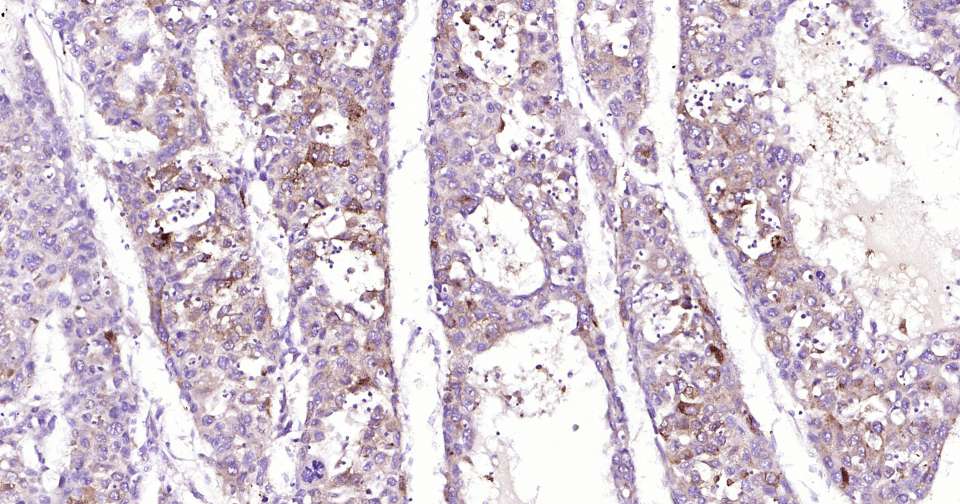

Immunohistochemical analysis of paraffin embedded human breast cancer tissue slide using IHC0313H (Human Nrf2 Kit).

Immunohistochemical analysis of paraffin embedded human cervical cancer tissue slide using IHC0313H (Human Nrf2 Kit).

Immunohistochemical analysis of paraffin embedded human hepatocellular carcinoma tissue slide using IHC0313H (Human Nrf2 Kit).